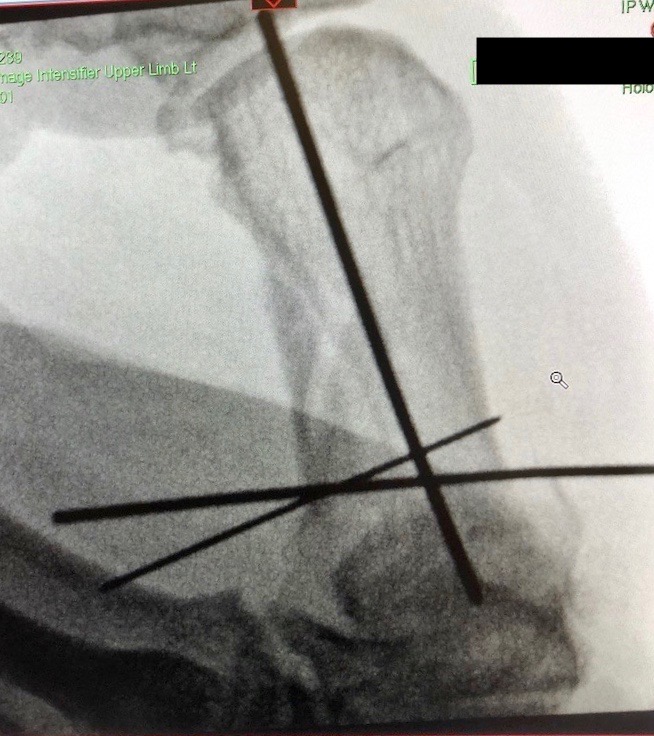

Didn't think I would make this month happen because of this:

View attachment 1813116View attachment 1813117

View attachment 1813118View attachment 1813119

Dislocated and bust thumb - pinned and healing slowly

Cracked on to complete both awards